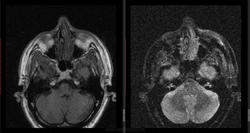

- https://radiomed.ru/sites/default/files/styles/case_slider_image/public/user/16807/5_9.jpg?itok=VBsarq3_

- https://radiomed.ru/sites/default/files/styles/case_slider_image/public/user/16807/6_6.jpg?itok=kUd4dXBb

дифференциальная диагностика ganglion ,нодулярный фасциит,нейрофиброма,дерматофиброма